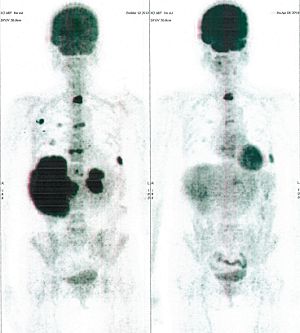

CASE NO: 2 (HEPATOCELLULAR CARCINOMA)

A 40+ man with hepatocellular carcinoma, an incurable cancer. After 2 treatment, the activity of the hepatocellular carcinoma is less.

CASE NO: 2 (HEPATOCELLULAR CARCINOMA) - After a few more treatments

After another few treatment, the activity of the hepatocellular carcinoma is much less. The patient never came back for further treatment, but this case, and case no: 1, shows that incurable hepatocellular carcinoma, often seen in hepatitis B and C patients, can be cured.